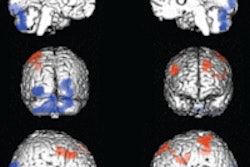

![]() |

| Results of the SPM analysis correlating changes in BOLD signal with subjective ratings of "mind-racing" produced by methamphetamine. Correlated activations (shown within the white circles) were found in (a) the medial prefrontal cortex (rostral anterior cingulated cortex), (b) ventral striatum, and (c) orbitofrontal cortex. The p values shown are with the small-volume correction (SVC) procedure. Image courtesy of Dr. Birgit Völlm and Neuropsychopharmacology, September 2004, Vol. 29:9, pp. 1715-1722, figure 3, copyright 2004 by the Nature Publishing Group. |

The results showed that all the subjects reported a mind-racing experience within three minutes of meth infusion. On fMRI, there were significant activations in the medial part of the orbitofrontal cortex and in the rostral part of the anterior cingulate cortex. The fMRI signal and mind-racing ratings correlated in the caudate nucleus and in the rostral part of the anterior cingulate cortex.

The findings are significant in light of previous research showing a connection between the orbitofrontal cortex and drug addiction, the authors said. Because their subjects had no previous experience with psychostimulants, the results were not complicated by craving or cued recall, which are common in drug-dependent individuals.